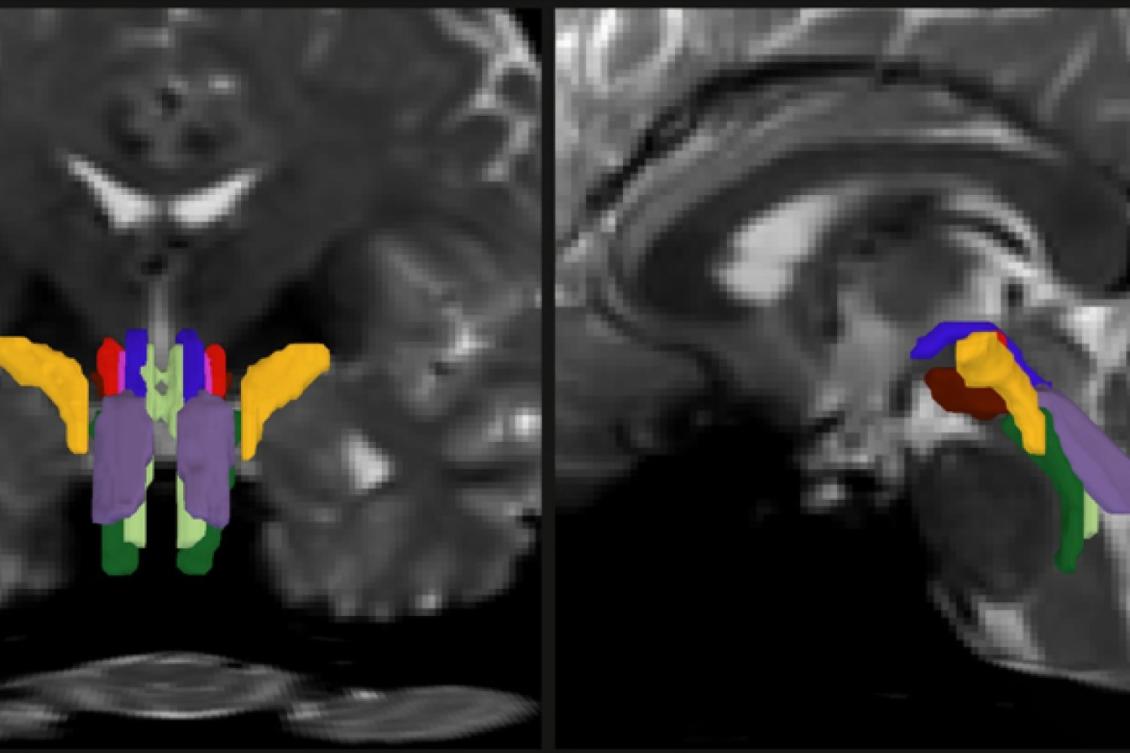

Researchers have developed a new way to resolve distinct bundles of nerve fibers in the brainstem. In this detail of a figure from the paper offering two different cross-section views of a human brain, individual bundles are segmented and color-coded.

The signals that drive many of the brain and body’s most essential functions — consciousness, sleep, breathing, heart rate, and motion — course through bundles of “white matter” fibers in the brainstem, but imaging systems so far have been unable to finely resolve these crucial neural cables. That has left researchers and doctors with little capability to assess how they are affected by trauma or neurodegeneration.

In a new study, a team of MIT, Harvard University, and Massachusetts General Hospital researchers unveil AI-powered software capable of automatically segmenting eight distinct bundles in any diffusion MRI sequence.

As part of his thesis work to better understand the neural mechanisms that underpin consciousness, Olchanyi wanted to develop an AI algorithm to overcome these obstacles. BSBT works by tracing fiber bundles that plunge into the brainstem from neighboring areas higher in the brain, such as the thalamus and the cerebellum, to produce a “probabilistic fiber map.” An artificial intelligence module called a “convolutional neural network” then combines the map with several channels of imaging information from within the brainstem to distinguish eight individual bundles.